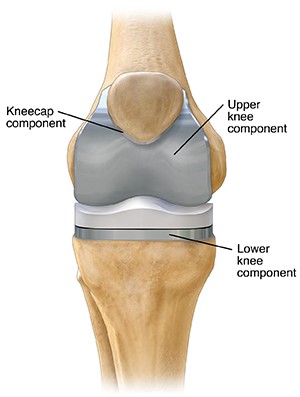

A knee prosthesis

A knee prosthesis lets your knee bend easily again. The roughened ends of the thighbone and shinbone and the underside of the kneecap are replaced with metal and strong plastic parts. With new smooth surfaces, the bones can once again glide freely without pain. A knee prosthesis does have limits. But it can let you walk and move with greater comfort.